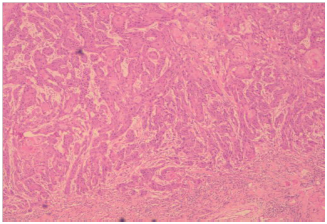

The patient was then planned for a partial penectomy along with transurethral resection of the bladder tumour. The patient underwent a partial penectomy (Figure 3) along with transurethral resection of the bladder tumour. The pathology results from the TURBT (Transurethral resection of bladder tumour) revealed a low grade transitional cell carcinoma, with no muscle invasion (Figures 4 & 5). Penile resection specimen showed a moderately differentiated squamous cell carcinoma with no lympho vascular invasion with the re-sected margin being negative for tumour (Figures 6 & 7). The TNM stage of the penile and bladder tumour was T1N0M0 and T1N0M0, respectively. The final diagnosis was double primary cancer of the penis and bladder. The follow-up check Cystoscopy and CT scan of the abdomen and pelvis done six months after the operation showed no evidence of recurrence. The inguinal lymphadenopathy too subsided post-operative lyon antibiotics treatment, presumably being reactive in origin. Patient reports no lower urinary tract symptoms and has good stream and minimal post void volume.8

Figure 4 Low power magnification of penile growth.

Figure 5 High power magnification of penile growth.